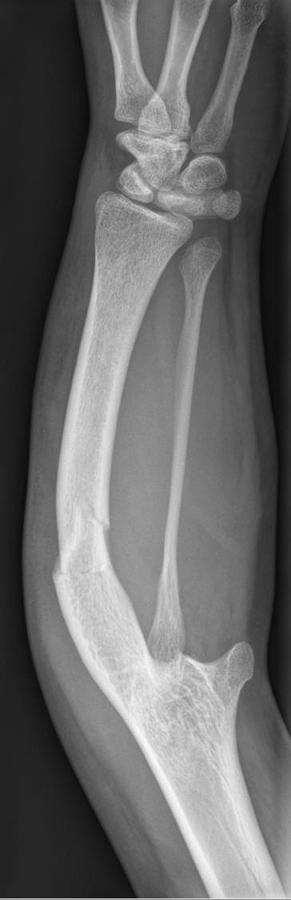

Ulna hypoplasia-intellectual disability syndrome is a very rare genetic disorder which is characterized by shortening of the arms associated with ulnar aplasia/hypoplasia, bilateral clubbed feet, widespread nail aplasia/hypoplasia, and severe psychomotor delays with intellectual disabilities.[1][2][3] It has only been described in two siblings born to consanguineous Arab parents. It is thought to be inherited in an autosomal recessive manner.[4][5]